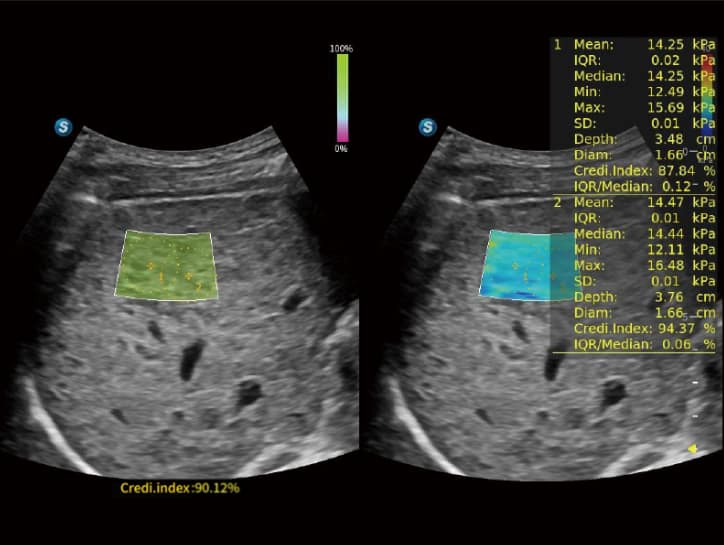

• S-SWE (Shear Wave Elastography): Ermöglicht die quantitative Beurteilung der Leberfibrose inklusive einer Qualitätskarte zur Stärkung des Diagnosevertrauens.